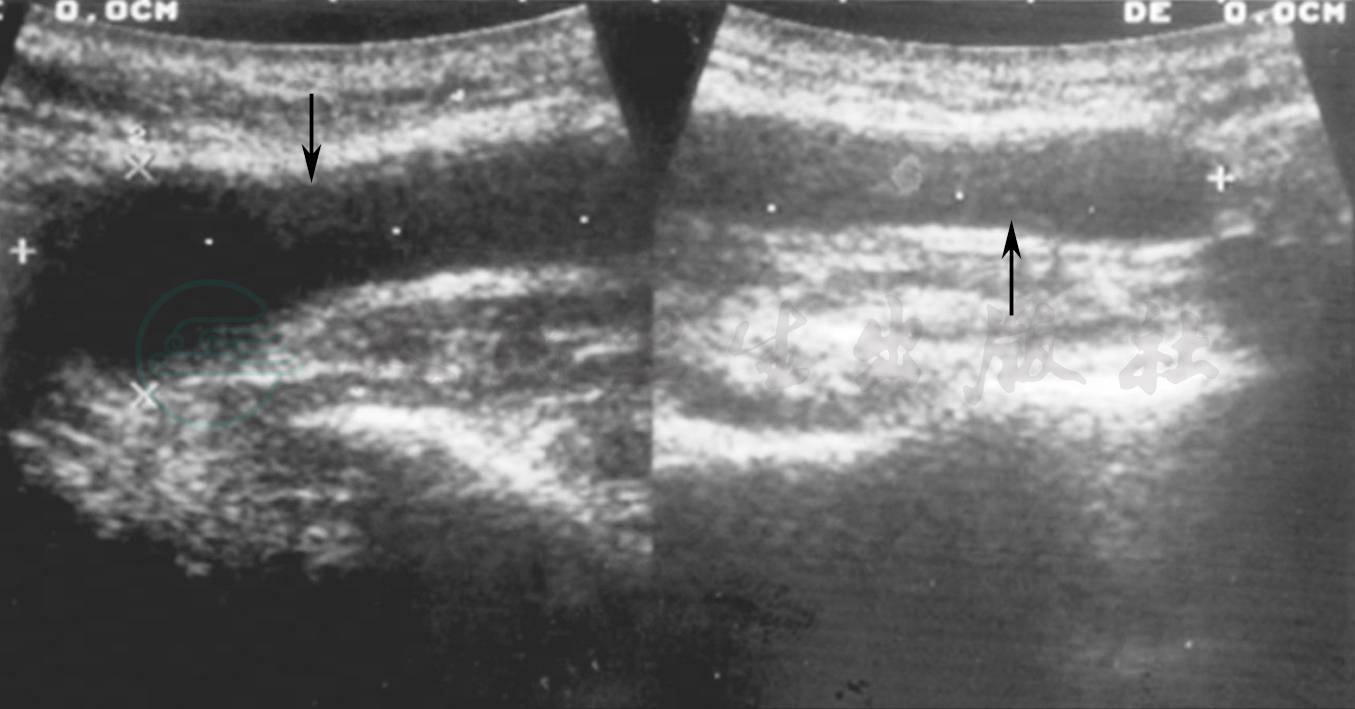

唾液腺造影显示腮腺或下颌下腺主导管囊状扩张,可以延及某些叶间导管。无继发感染史者,导管壁光滑(图1、2)。有继发感染史者,导管壁变得不光整。B超显示导管所在处无回声团块,呈管状结构(图3)。CT表现为沿导管走行方向呈管状的软组织病变(图4)。

图3先天性腮腺导管扩张(声像图)

腮腺主导管呈囊状扩张的无回声结构